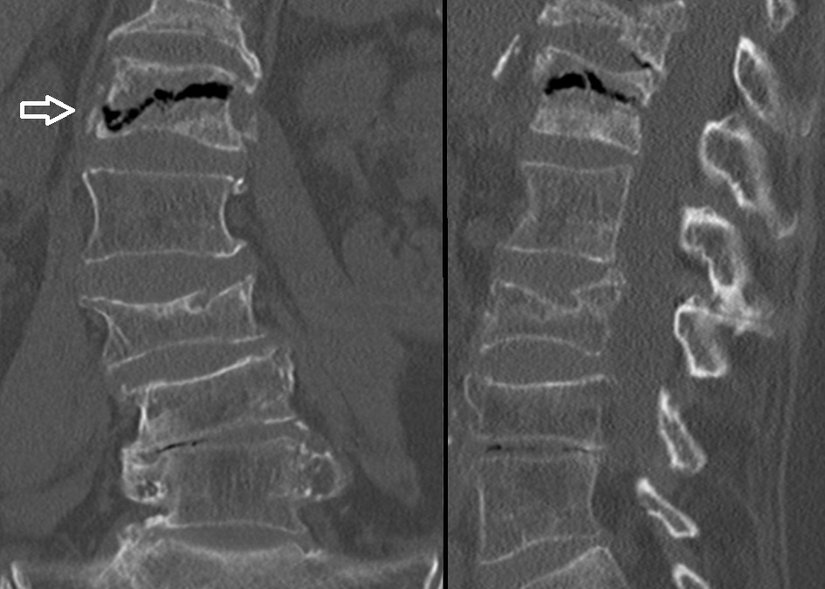

Bilgisayarlı Tomografi (BT)

BT taramaları, azaltılmış zayıflamanın merkezi veya çevresel alanlarını gösterir. Yeniden biçimlendirilmiş sagital ve koronal görüntüler subkondral kırıkları ve eklem yüzeyinin çökmesini gösterir. Düz radyografik bulgular normal olduğunda BT bulguları kemik nekrozu ile ilişkili ince trabeküler düzensizlik gösterebilir. Eklem yüzeylerinin çökmesi veya burkulması daha ileri hastalığı gösterir ve tedavi seçimini etkiler.

Konvansiyonel radyografide olduğu gibi, BT kemik enfarktlarının tespitinde duyarlı değildir. Bununla birlikte, BT taramaları, düz radyografilerde olduğundan daha erken kemik enfarktüsünün teşhis edilmesine yardımcı olabilir. BT'nin kemik enfarktüsü tanısında duyarlılığı MRG ve kemik sintigrafisinden daha düşüktür.

Düz radyografide olduğu gibi, bir kemik enfarktüsünün erken BT özellikleri, özellikle uzun kemiklerin metafiz bölgesinde özgünlükten yoksundur. Belirsiz radyolüsensler enfeksiyonları ve neoplastik süreçleri taklit edebilir.

BT taraması diğer tekniklerin tamamlayıcısıdır, ancak radyonüklid görüntüleme veya MRG kadar hassas değildir. Düz radyografik bulgular normal olduğunda BT taramaları kemik nekrozu ile birlikte ince trabeküler düzensizlik gösterebilir. Orak hücre hastalığı olan hastalarda kemik enfarktüsünü osteomiyelitten ayırmada ultrasonografi faydalı olabilir.